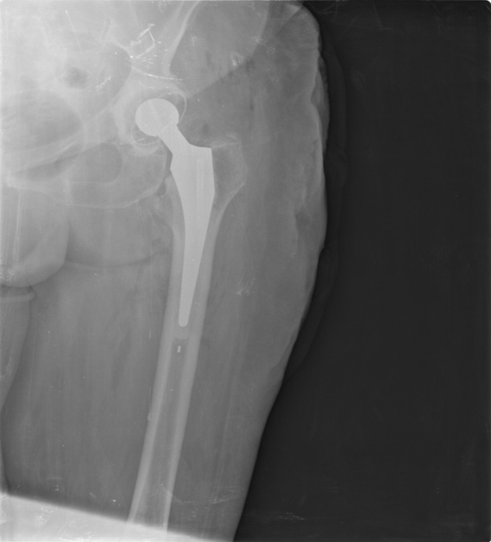

The second day the patient was operated. We have chosen a hip direct lateral approach (Hardinge) with the patient in supine position. Considering the age of the patient and her associated conditions we opted for a cemented total hip arthroplasty in order to have the best results (Figure 4). The second day postoperative the patient started rehabilitation with bed side exercises and at third day postoperatively weight bearing walk was possible. Follow-up at 45th day, the patient had an overall good recovery with a hip Harris score of 78.

Figure 4: The postoperative recovery was good and at sixth day the patient was discharged.